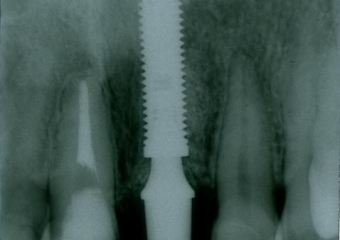

Raio X inicial

Raio X com implante e prótese provisória fixa